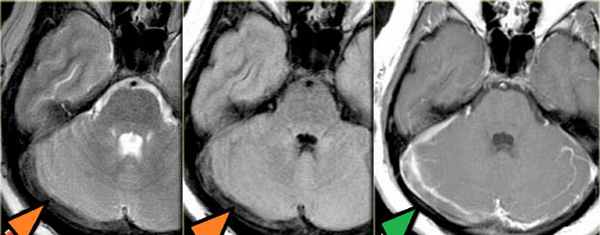

Тромбоз правого поперечного синуса – гипоинтенсивные участки по Т2 (внутриклеточный дезоксигемоглобин).

Для подтверждения тромбоза венозного синуса и определения точной локализации и протяженности тромба необходимо проведение МР-венографии.

МР-венография – отсутствие визуализации кровотока в правом поперечном синусе и яремной вене.